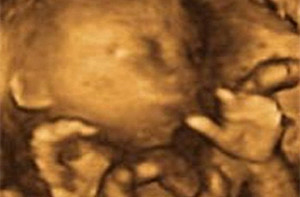

La longitud del embrión es de 3 a 4 centímetros y su peso, unos 5 gramos. Podemos determinar el peso del embrión. El embrión cada vez tiene más forma humana y se distingue los brazos y los antebrazos, así como las manos que se abren y se cierran y están a la altura de la boca. La cara es más redondeada. Los ojos permanecen cerrados y la boca se abre y se cierra. La mineralización de los huesos progresa intensamente, sobre todo en el cráneo.